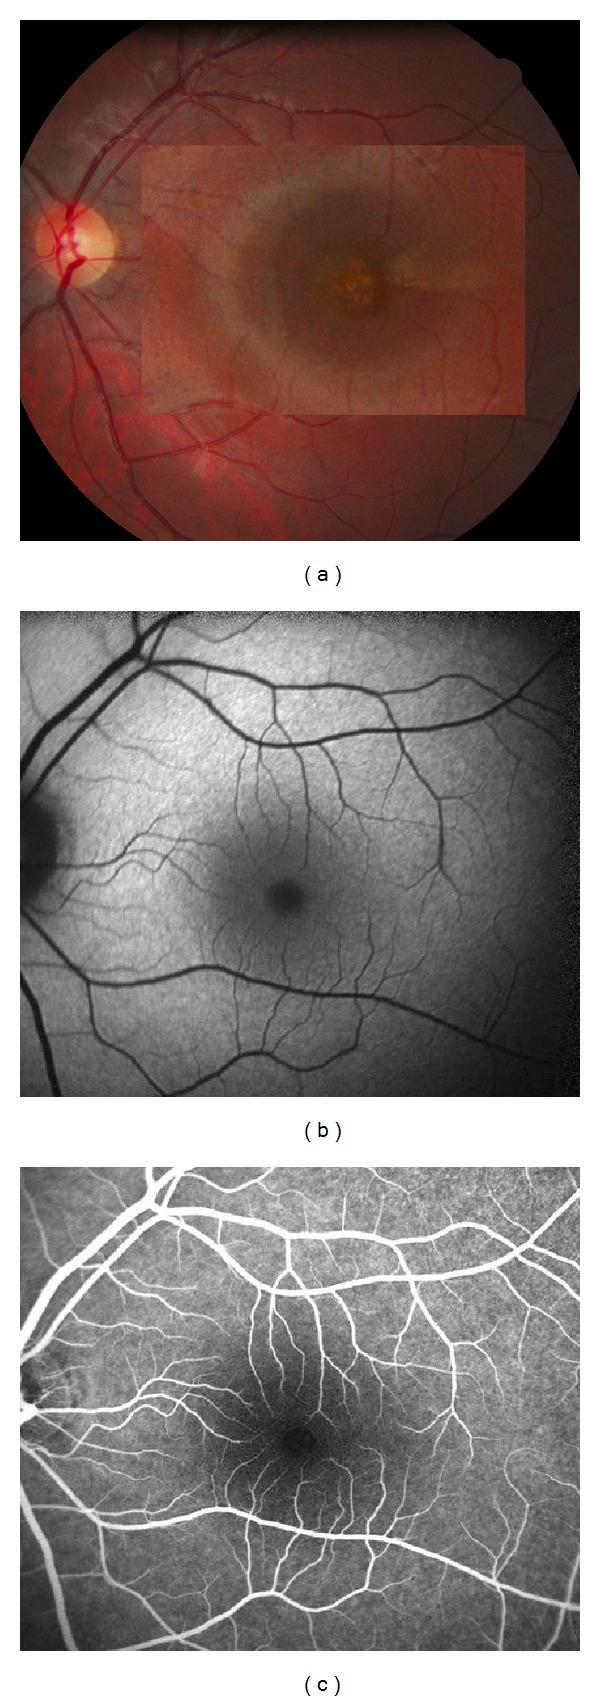

Purpose. To report B-scan and "En-face" spectral-domain optical coherence tomography (SD-OCT) findings in acute retinal pigment epitheliitis (ARPE). Methods. Two patients (3 eyes) with ARPE were examined. Fluorescein and indocyanine green (ICGA) angiography, B-scan, and "En-face" SD-OCT were performed in each patient at initial and follow-up visits. Results. Both patients presented with acute onset of blurred vision, and one with bilateral involvement. B-can OCT revealed disruption of the macular retinal pigment epithelial (RPE) inner band layer and photoreceptors' inner and outer segment (IS-OS) junction. Hyperreflective dots were observed in the outer nuclear layer (ONL) above the RPE/IS-OS disruption. Just around these hyperreflective dots, slight thickening of the hyperreflective IS/OS junction was observed. During the late phase, indocyanine green angiography (ICGA) showed a macular cockade-like hyperfluorescent halo. "En-face" OCT showed the same cockade-like appearance with a hyporeflective center and a hyperreflective border matching the pattern observed on ICGA. At followup, as vision improved without treatment, B-scan OCT demonstrated progressive resolution of the hyperreflective and disrupted lesions; "en-face" OCT also showed disappearance of the macular cockade-like halo with a transient discrete hyperreflective macular star at the RPE level in one eye. Conclusion. "En-face" OCT associated with B-scan SD-OCT analysis appears to be very helpful in the diagnosis and followup of ARPE. The pathophysiology of ARPE remains complex and still poorly understood. These techniques help define the location and extent of structural damage occurring in this disease.

目的。报告急性视网膜色素上皮炎(ARPE)的B超和“表面”光谱域光学相干断层扫描(SD-OCT)结果。方法。对2例(3只眼)ARPE患者进行检查。每位患者在初诊和随访时均进行荧光素和吲哚菁绿(ICGA)血管造影、B超和“表面”SD-OCT检查。结果。2例患者均急性起病,视力模糊,其中1例为双眼受累。B超OCT显示黄斑区视网膜色素上皮(RPE)内带层及光感受器内、外节(IS-OS)连接中断。在RPE/IS-OS中断上方的外核层(ONL)观察到高反射点。就在这些高反射点周围,观察到高反射的IS/OS连接稍有增厚。在晚期,吲哚菁绿血管造影(ICGA)显示黄斑区有帽徽样高荧光晕。“表面”OCT显示相同的帽徽样外观,低反射中心和高反射边界与ICGA上观察到的模式相符。随访时,未经治疗视力改善,B超OCT显示高反射和中断病变逐渐消退;“表面”OCT也显示黄斑帽徽样晕消失,其中1只眼在RPE水平出现短暂离散的高反射黄斑星。结论。“表面”OCT联合B超SD-OCT分析似乎对ARPE的诊断和随访非常有帮助。ARPE的病理生理学仍然复杂,仍知之甚少。这些技术有助于确定该疾病中结构损伤的位置和范围。